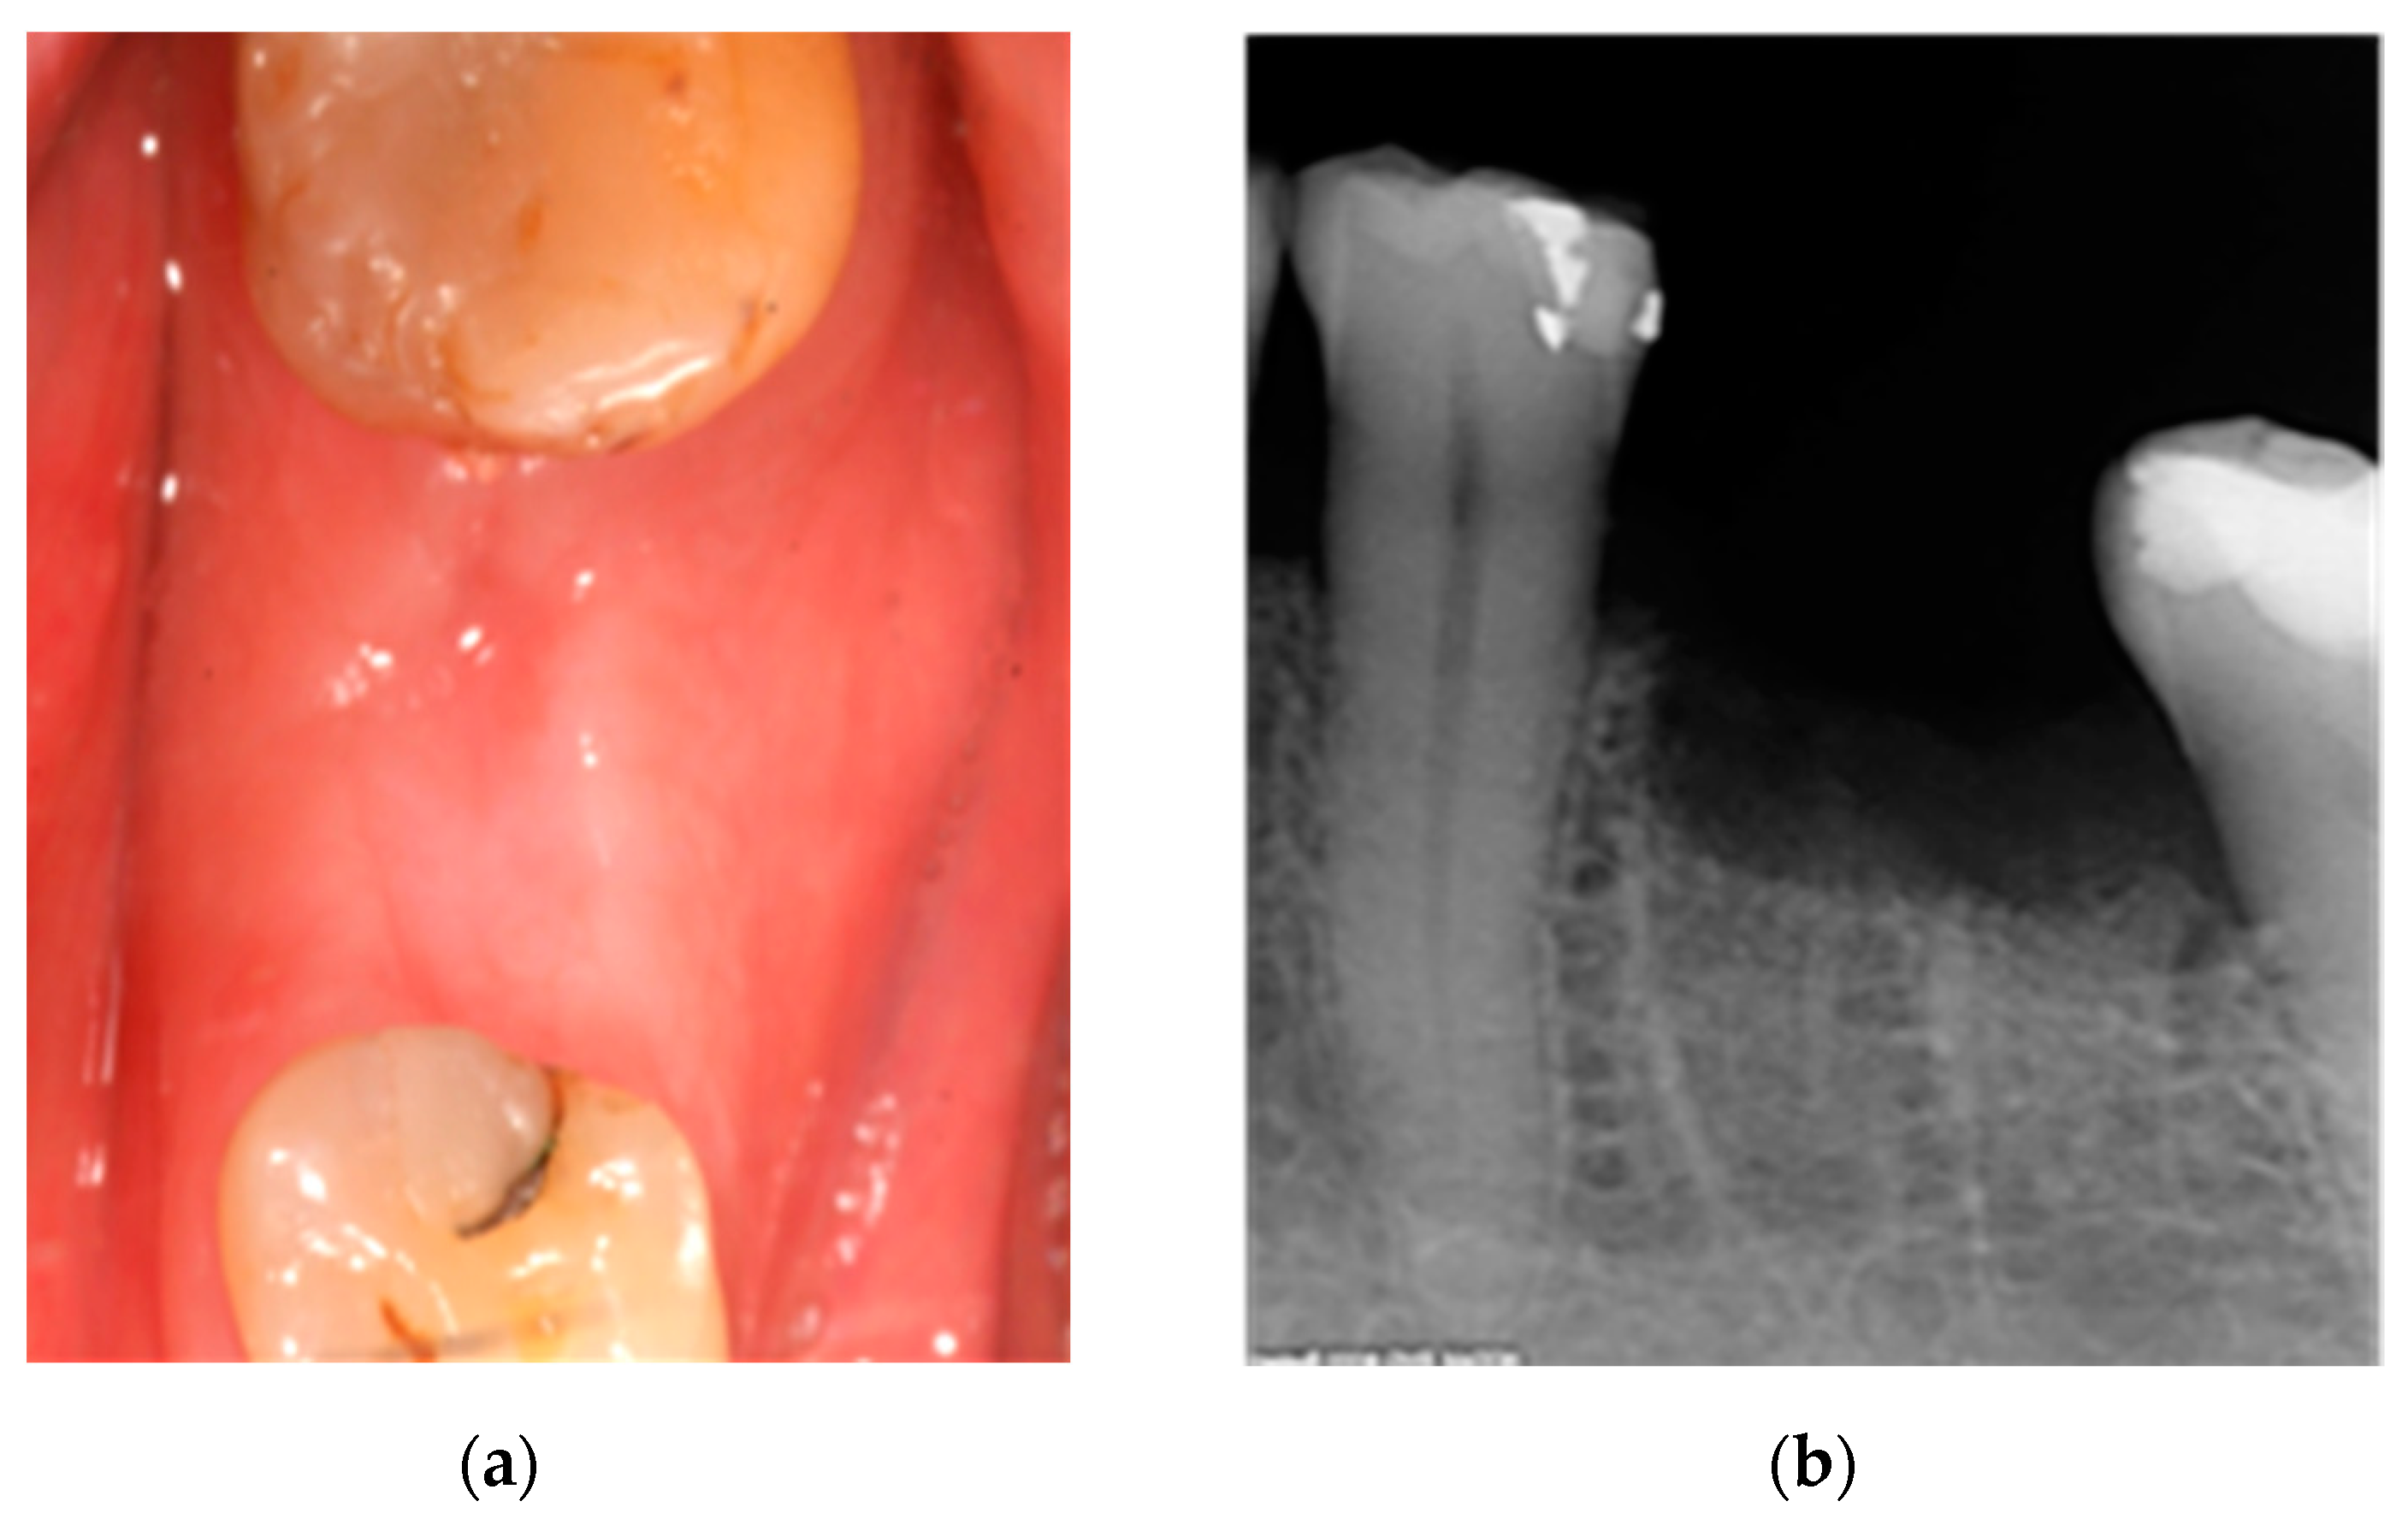

2.1. Case 1: Conservative Treatment

2.2. Case 2: Conservative Treatment Plus Surgery

2.3. Case 3: Conservative Treatment + SURGERY + PRF-L